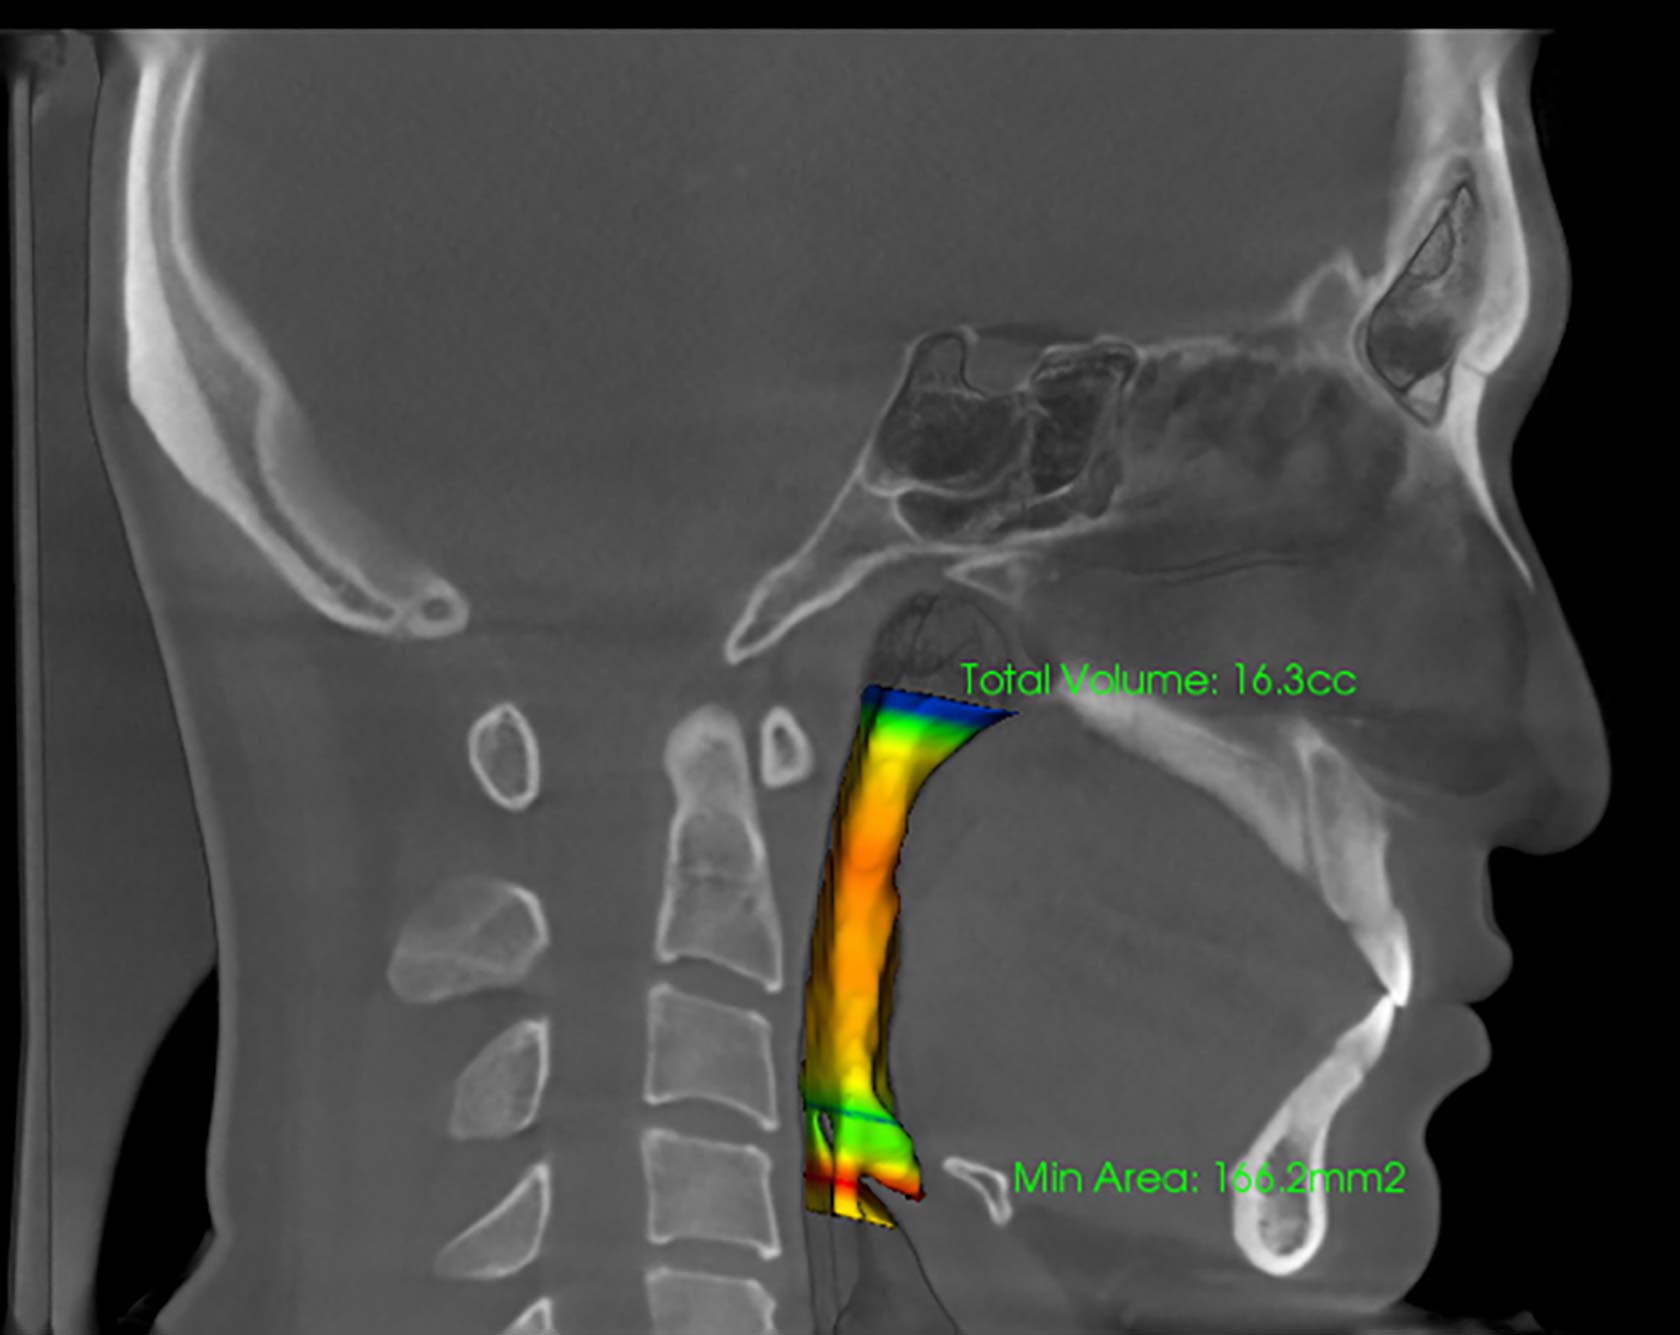

③レントゲン検査

(歯、顎の発育を診断します)

レントゲン写真を撮影し、各歯の状況や生え替わりの大人の歯の様子を確認します。なお撮影に使用する機器のX線量は従来のものの10分の1程度と非常に低いものですので、安心してお受けいただけます。